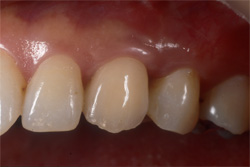

| 失った部分にインプラントを1本埋入します。従来は健全な両隣の歯を削ってブリッジを用いて治療していましたが、インプラントを用いると健全な歯を削ることなく治療を行うことが出来ます。 |

| インプラントの上のクラウンにより、あなたの咀嚼機能と自然な風貌が回復するでしょう。 |